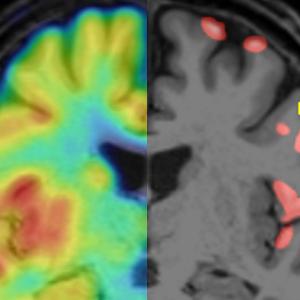

Multiple Sklerose: Nachweis veränderter grauer Substanz mittels PETForschende um Martin Kerschensteiner haben erstmals gezeigt, dass sich mit der Positronen-Emissionstomografie (PET) der Synapsenverlust in den MS-Läsionen der Großhirnrinde abbilden lässt.